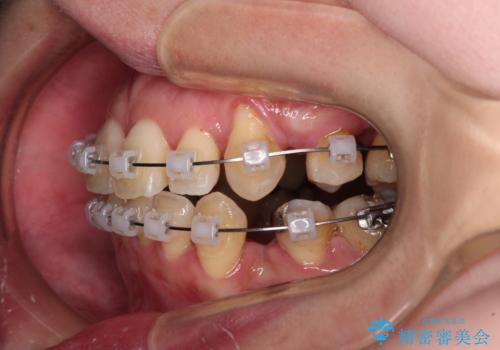

【モニター】上下の八重歯を治したい ワイヤー装置による矯正治療

- クリアブラケット

- 上下前歯のデコボコを気にして来院された患者様です。

デコボコが強いため、非抜歯で矯正をすると出っ歯仕上がりとなるため、上下左右の第一小臼歯4本を抜歯することとしました。